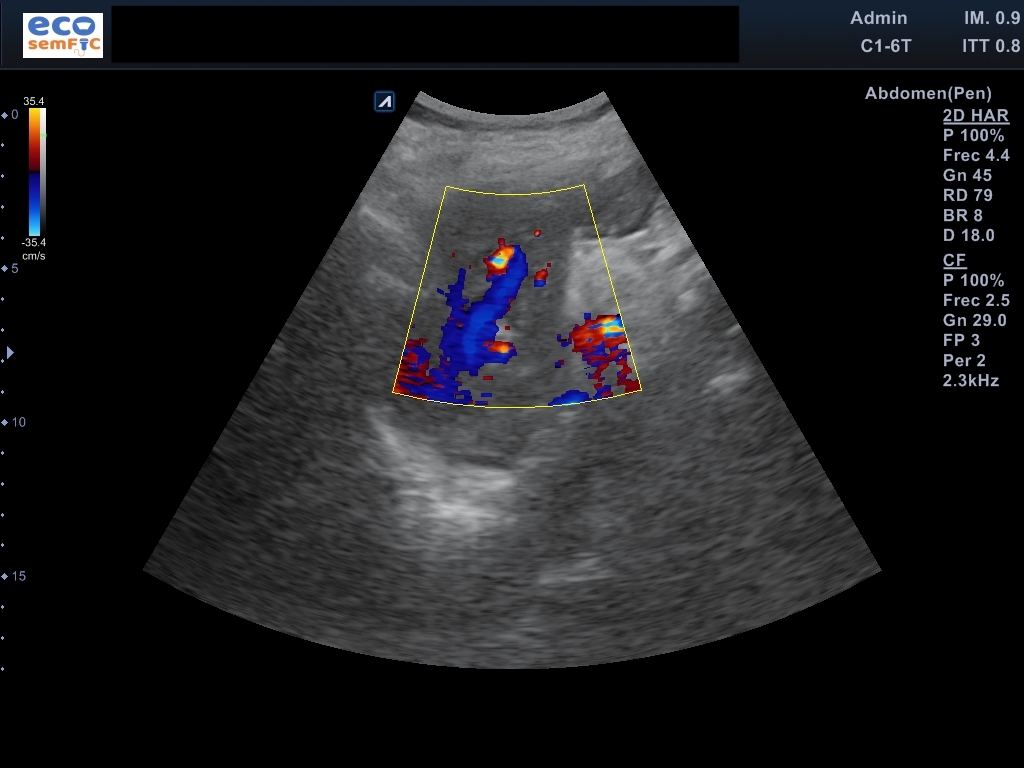

Limitada por poca colaboración, pero aceptable. En las áreas accesibles, hígado de superficie lisa y contorno regular, heterogéneo sin aparentes LOEs. Radicales intrahepáticos dependientes del conducto hepático derecho ectásicos. Colédoco proximal de 8,3 mm y distal de 14,3 mm a nivel de la cabeza del páncreas. Marco duodenal ocupado por contenido sólido aperistáltico en este momento. Páncreas visualizado en toda su extensión con Wirsung patente no dilatado, sin lesiones focales. Riñones de aspecto senil, conservan el grosor cortical y diferenciación parénquima-seno. Bazo homogéneo no aumentado ni lesiones parenquimatosas. Ausencia líquido libre o colecciones en áreas exploradas.